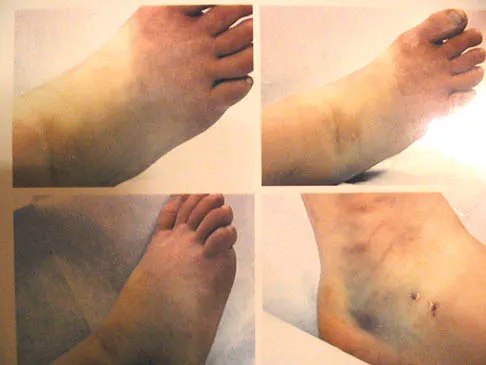

An 11-year-old boy has had a fever and pain and swelling over the lateral aspect of his right ankle for the past 3 days. Examination reveals warmth, swelling, and tenderness over the lateral malleolus, and he has a temperature of 103.2 degrees F (39.5 degrees C). Laboratory studies show a WBC count of 13,200/mm3 with 61% neutrophils, an erythocyte sedimentation rate of 112 mm/h, and a C-reactive protein of 15.7. Radiographs and a T2-weighted MRI scan are shown in Figures 13a through 13c. Aspiration yields 1 mL of purulent fluid. Management should now consist of

Explanation